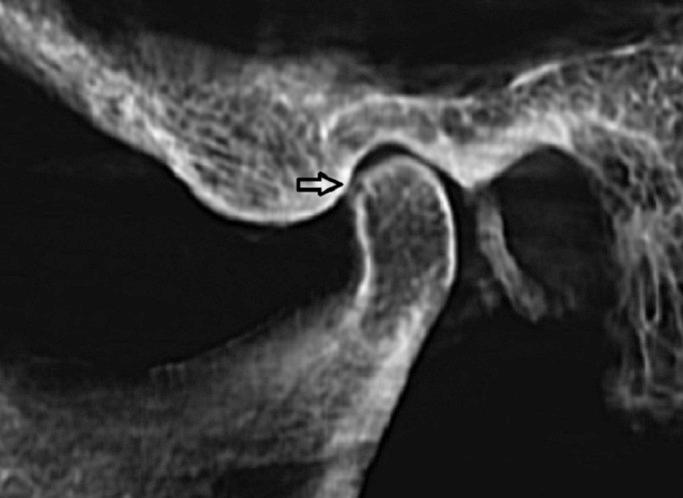

Radiographic examination is one of the most important parts of the clinical assessment routine for temporomandibular disorders. The aim of this study was to compare the diagnostic accuracy of cone-beam computed tomography(CBCT) with panoramic radiography and spiral computed tomography for the detection of the simulated mandibular condyle bone lesions.

The sample consisted of 10 TMJs from 5 dried human skulls. Simulated erosive and osteophytic lesions were created in 3 different sizes using round diamond bur and bone chips, respectively. Panoramic radiography, spiral tomography and cone-beam computed tomography were used in defect detection. Data were statistically analyzed with the Mann-Whitney test. The reliability and degrees of agreement between two observers were also determined by the mean of Cohen's Kappa analysis.

CBCT had a statistically significant superiority than other studied techniques in detection of both erosive and osteophytic lesions with different sizes. There were significant differences between tomography and panoramic in correct detection of both erosive and osteophytic lesions with 1mm and 1.5 mm in size. However, there were no significant differences between Tomography and Panoramic in correct detection of both erosive and osteophytic lesions with 0.5 mm in size.

CBCT images provide a greater diagnostic accuracy than spiral tomography and panoramic radiography in the detection of condylar bone erosions and osteophytes. Key words:Bone defect, Condyle, CBCT, Panoramic, radiography.

影像学检查是颞下颌关节紊乱病临床评估常规中最重要的部分之一。本研究的目的是比较锥形束计算机断层扫描(CBCT)与全景放射摄影和螺旋计算机断层扫描在检测模拟下颌髁突骨病变方面的诊断准确性。

样本包括来自5个干燥人类头骨的10个颞下颌关节。分别使用圆形金刚石钻和骨屑制作了3种不同大小的模拟侵蚀性和骨赘性病变。在缺陷检测中使用了全景放射摄影、螺旋断层扫描和锥形束计算机断层扫描。数据采用曼-惠特尼检验进行统计分析。两位观察者之间的可靠性和一致性程度也通过科恩卡方分析的平均值来确定。

在检测不同大小的侵蚀性和骨赘性病变方面,CBCT在统计学上比其他研究技术具有显著优势。在正确检测大小为1mm和1.5mm的侵蚀性和骨赘性病变方面,断层扫描和全景放射摄影之间存在显著差异。然而,在正确检测大小为0.5mm的侵蚀性和骨赘性病变方面,断层扫描和全景放射摄影之间没有显著差异。

在检测髁突骨侵蚀和骨赘方面,CBCT图像比螺旋断层扫描和全景放射摄影具有更高的诊断准确性。关键词:骨缺损;髁突;CBCT;全景;放射摄影。